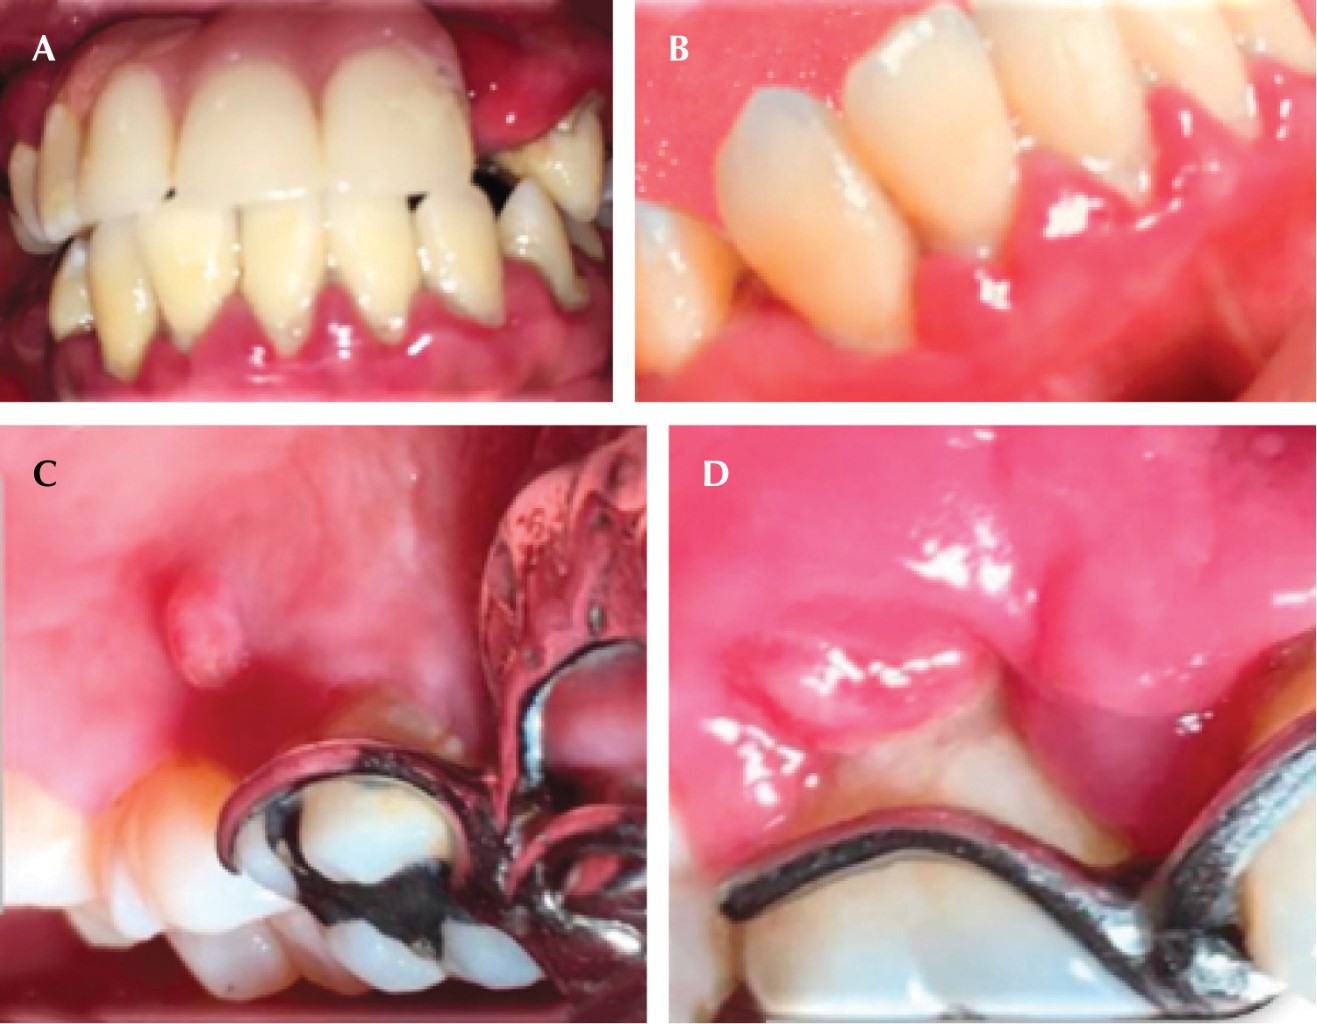

Una vez establecido el diagnóstico, se emitió el plan de tratamiento que consistió en realizar una fase I periodontal, alternando sus citas con el Hospital "Dr. Manuel Gea González" para el control de su glicemia. Después de modificar el tratamiento para la diabetes por parte del Hospital y realizando el control mecánico del biofilm microbiano, se comenzaron a observar cambios clínicos, como disminución del aumento de volumen (Figura 2A y C) y desaparición de los absceso periodontales (Figura 2B y D). Una vez que los niveles de glucosa se estabilizaron, se inició la fase II del nivel de tratamiento periodontal (extracciones, desbridamiento por colgajo con injerto óseo), se medicó a la paciente con doxiciclina (previo al procedimiento quirúrgico una cápsula de 100 mg cada 12 horas, segundo día hasta el séptimo día, una cápsula de 50 mg cada 12 horas) y ketorolaco de 10 mg, una tableta cada ocho horas o sólo en caso de dolor. Después de estabilizar periodontalmente a la paciente se incorporó a la terapia de mantenimiento y se dio inicio el tratamiento de rehabilitación, elaborando una prótesis parcial removible (Figura 3A-C). Después de dos años de adhesión al tratamiento, la paciente dejó de asistir a consulta.